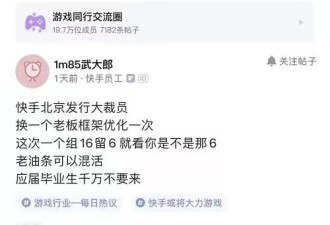

得出以上结论,研究人员主要是通过追踪老人大脑中脑白质高信号(WMH)和腔隙的变化来实现的。

△A为脑白质高信号;B为腔隙

以上两种现象都是脑小血管病(CSVD)的主要表现。

这种疾病在老年人群体中高发,会表现出情感障碍、认知功能下降等症状,

也就是说,当老人的大脑中出现脑白质高信号、腔隙变多变大等情况,就意味着老人的大脑可能在发生退化。